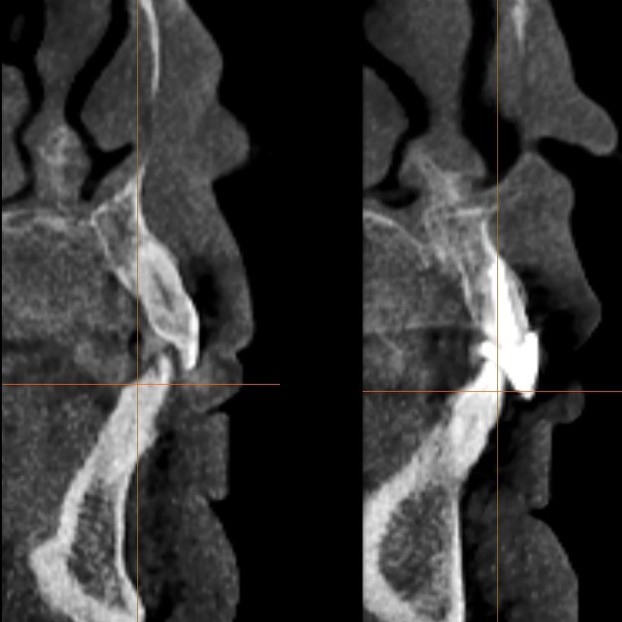

Implant restoration in the esthetic zone often requires well-coordinated interdisciplinary care in order to achieve ideal treatment results. This is especially the case when implants are planned to replace periodontally hopeless teeth. When teeth are extracted, we can typically anticipate 2mm of facial recession. If implants are to be placed following the extraction of hopeless teeth with an already existing gingival height discrepancy, the discrepancy will likely be exacerbated.

Extraction after forced eruption can allow for a much more favorable implant site compared with extraction alone. This is possible because the tension applied to the periodontal ligament during orthodontic tooth movement stimulates osteoblastic activity to induce new bone formation. As the tooth moves coronally during extrusion, soft tissue and bone attached to the periodontal fibers migrate in the same direction. As a result, forced eruption can be used to enhance the quality and quantity of both hard and soft tissue of future implant sites.

The special report presented below illustrates how orthodontic extrusion was successfully used to improve the periodontal architecture prior to the placement of two adjacent implants in the esthetic zone and thus allowed for a more ideal restorative result.